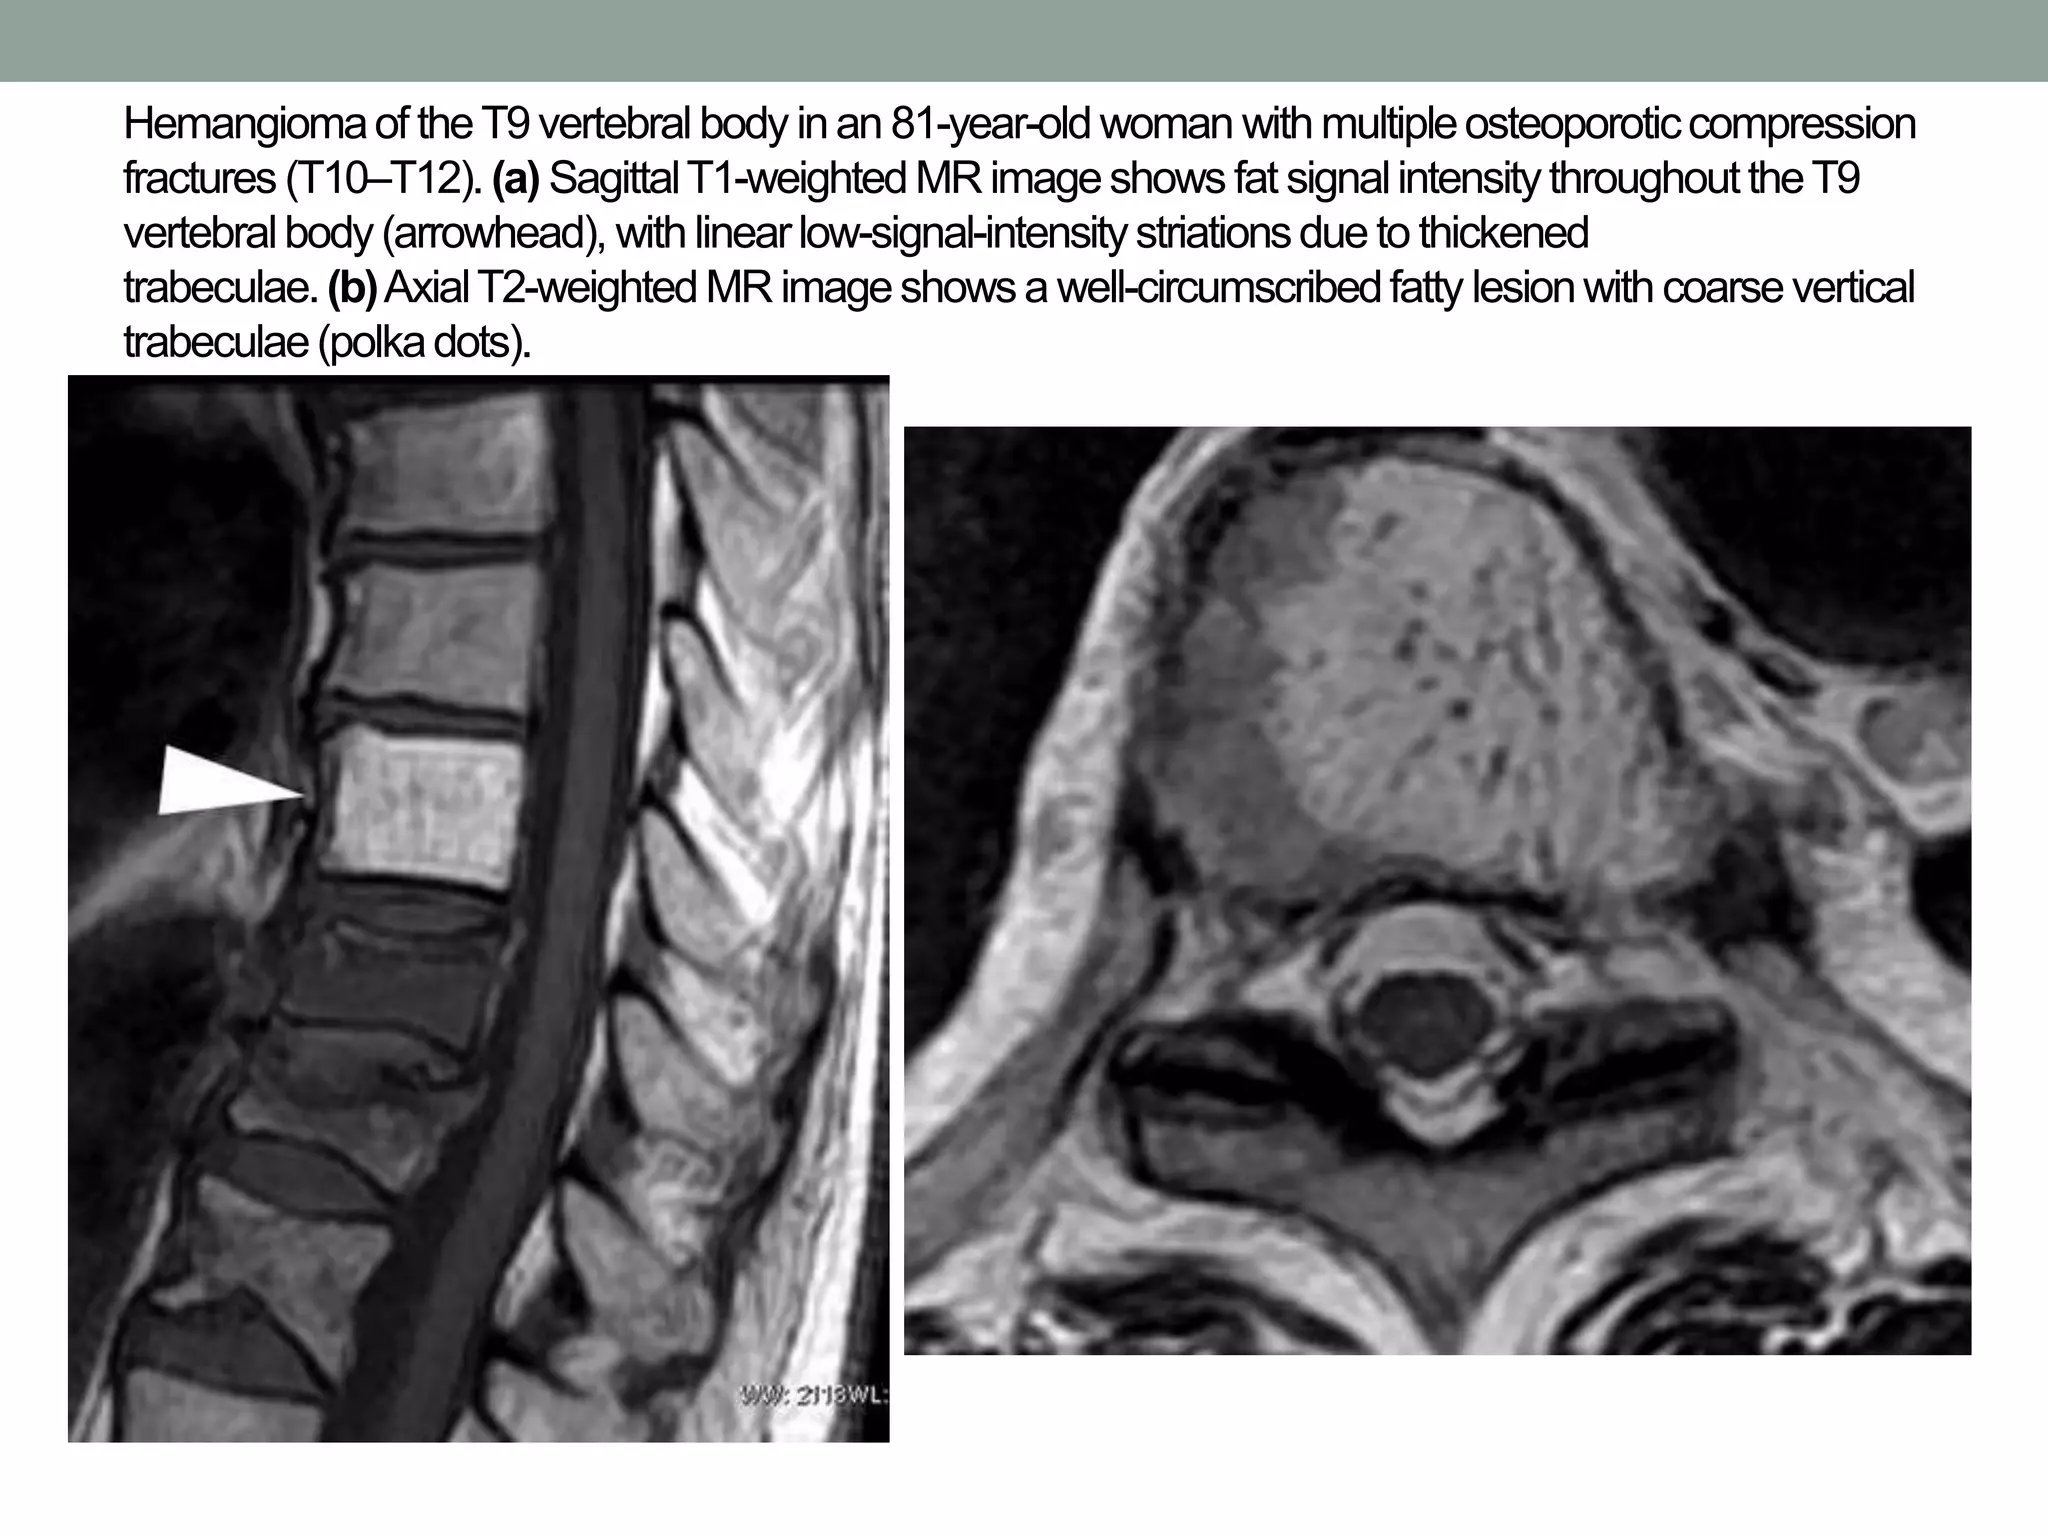

Hemangiomaof theT9vertebralbody inan 81-year-oldwoman withmultipleosteoporoticcompression

fractures (T10–T12). (a) SagittalT1-weightedMR imageshows fat signalintensitythroughouttheT9

vertebralbody(arrowhead), with linearlow-signal-intensitystriationsdue to thickened

trabeculae.(b)AxialT2-weightedMR imageshowsa well-circumscribedfatty lesionwith coarsevertical

trabeculae(polkadots).